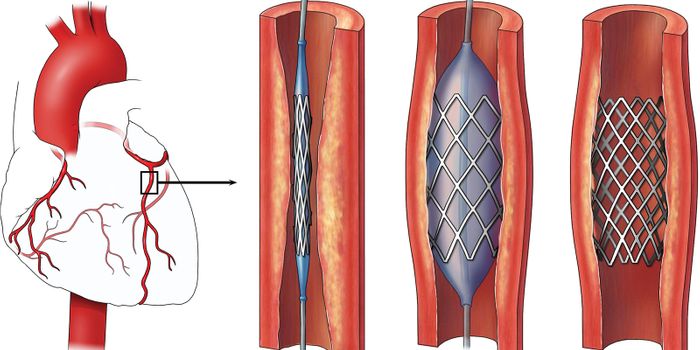

JAN 14, 2016CardiologyThe aortic valve regulates blood flow by opening and closing, and when it stops working an aortic valve replacement (AVR ...

JUN 14, 2016CardiologyMedication to dissolve blood clots and various surgical procedures can be done to reverse damage done to arteries with o ...

MAR 19, 2015CardiologyA technique used to clear blood clots from arteries to the heart in about 20 percent of patients undergoing angioplasty ...